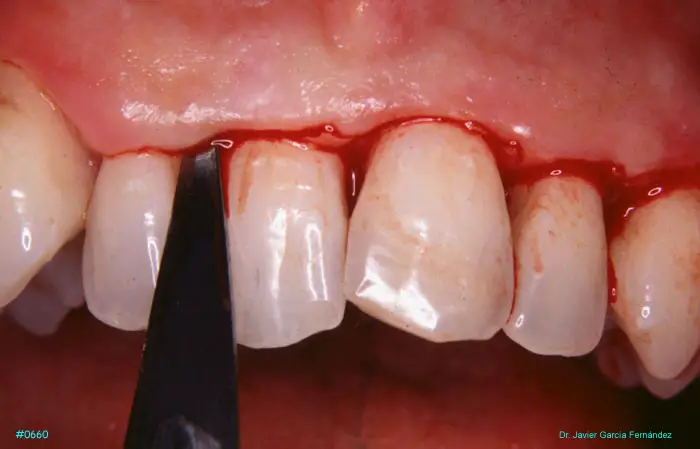

Atlas of Surgical Techniques in Periodontics. Chapter III. Atlas de Técnicas Quirúrgicas en Periodoncia

image47